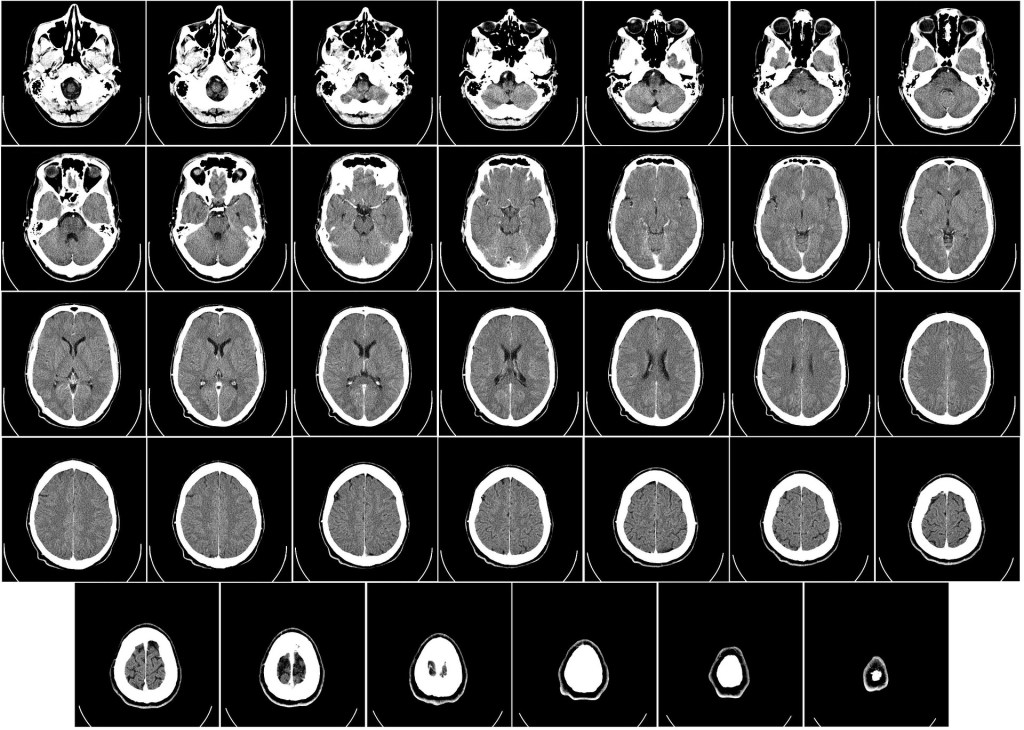

WikiImages (2012, 19 décembre). Tomographie par ordinateur d’un cerveau [image en ligne]. Pixabay. https://pixabay.com/images/id-62942/